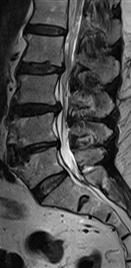

With degeneration of the joints between the vertebra, there is some collapse of the intervertebral disc and the resulting coming together of the vertebrae , along with thickening of the ligaments and overgrowth of the bone create a situation whereby the space available within the canal and foramen is reduced, thereby compromising the nervous structures.

This condition causes a situation of chronic nerve dysfunction called spinal canal stenosis.

Since the vertebral joints are most mobile at the cervical and lumbar levels, most of the degenerative changes occur at these level and hence , the condition of spinal canal stenosis mostly involves the neck and the low back.